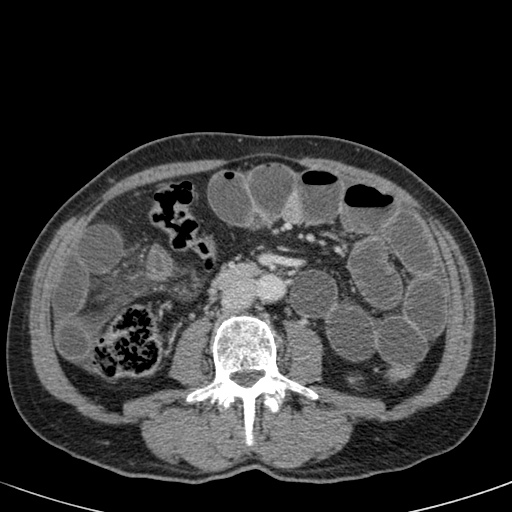

Tắc ruột dạng quai kín với các quai ruột giãn xếp theo hình nan hoa. Có dày thành ruột và phù nề mạc treo gợi ý thiếu máu cục bộ

Một hình ảnh quan trọng khác của tắc ruột dạng quai kín là các quai ruột non giãn xếp theo hình nan hoa với các mạch máu mạc treo hội tụ về một điểm trung tâm.

Hình ảnh này hầu như luôn do xoắn ruột non gây ra.

Các dấu hiệu thiếu máu cục bộ trong tắc ruột dạng quai kín tương tự như ở bệnh nhân thiếu máu mạc treo do các nguyên nhân khác:

- dày thành ruột

- phù nề mạc treo

- cổ trướng

- sự ngấm thuốc của thành ruột trong thiếu máu cục bộ có thể bình thường, tăng hoặc giảm.

Ca lâm sàng bên trái cho thấy một bệnh nhân khác bị tắc ruột dạng quai kín.

Mặc dù các mạch máu ngấm thuốc tốt, nhưng dường như thành ruột không ngấm thuốc.

Các dấu hiệu thiếu máu cục bộ khác trong ca này bao gồm phù nề mạc treo và dày thành ruột.

Ruột bị nhồi máu được phát hiện trong quá trình phẫu thuật.

Nếu quai kín dài hơn và định hướng vuông góc với mặt phẳng cắt, chúng ta sẽ thấy một cụm quai ruột như trong ca lâm sàng bên trái.

Đôi khi điều này khó nhận biết chỉ trên các lát cắt ngang và các tái tạo mặt phẳng coronal hoặc sagittal có thể hữu ích.

Trong ca này, cũng có phù nề mạc treo và cổ